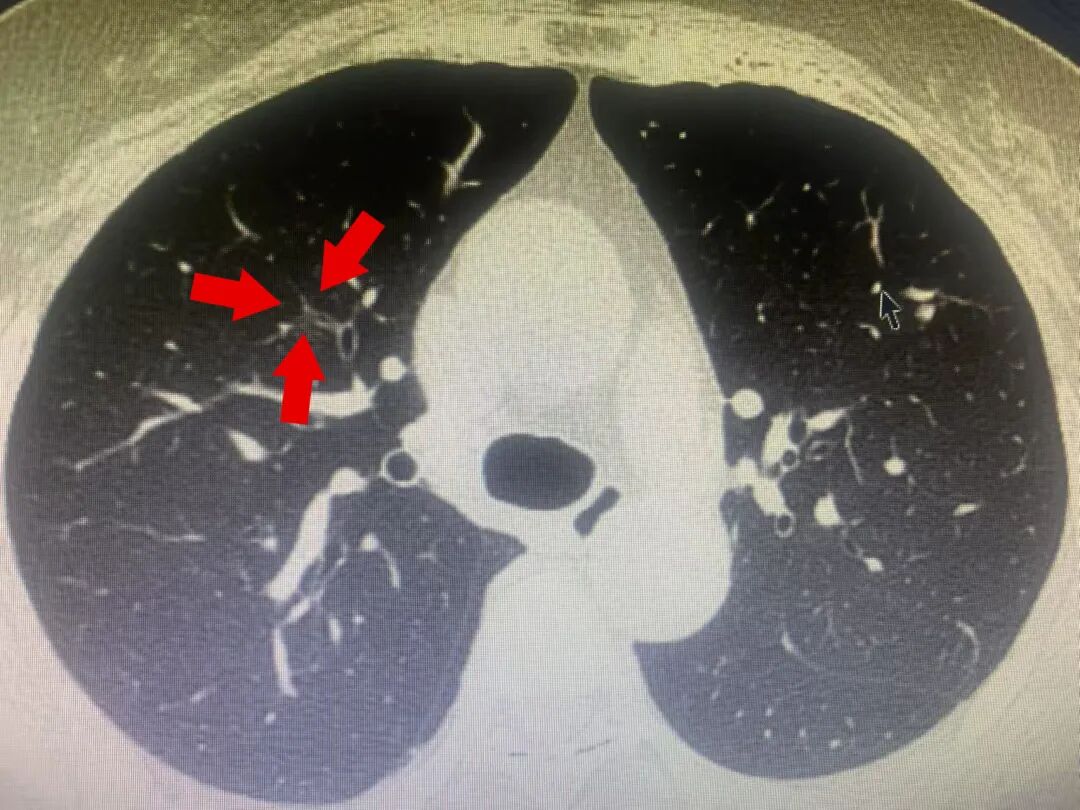

患者王某(化名),68岁女性,因长期接触油烟,属于肺癌高危人群。2025年01月04日体检时发现右肺结节

CT 检查显示:右肺存在一枚直径约8毫米的结节,该结节位置较深且邻近血管,使得活检操作风险较大,难以直接确定其性质

初步诊断为:结节性质不明,存在炎症或早期肿瘤的可能性,需进行进一步检查。